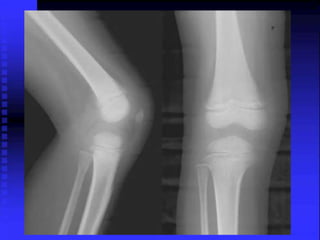

Case-9 A 4-y-oldboy presented to ER for pain in the Rt knee and limping. Hx of fall 2 days. X-rays Rt knee -- N. Dx: simple contusion. Back after 2 weeks with no improvement The pain was more localized in medial tibial plateau No fever ,WBC,CRP were normal, as were the new x-rays

• 126.

An ultrasound ofthe knee -- a small collection at the posterior side of the lateral tibial plateau appeared hypoechogenic. MRI revealed a slight hypersignal in the periphery, suggesting a subperiosteal collection in upper right tibial cortex The bone biopsy demonstrated no acute inflammation or tumoral lesion